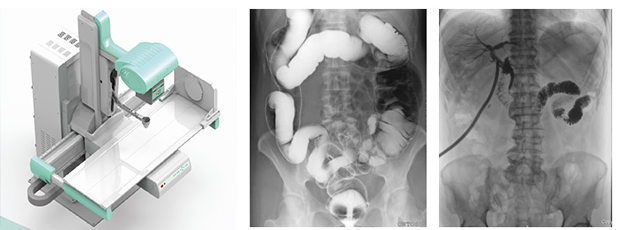

醫用DR,以其高質量圖像和高工作效率正逐漸替代現在傳統X線攝影技術, 成為當今數字X線攝影技術的代表,它可以對于人體內部組織進行透視、檢查,從而快速診斷患病情況,及時給予治療。作為一種全新X線成像技術,醫用DR使整個放射科特別是常規放射診斷的工作效率和經濟效益得到明顯提高。

醫用DR是臨床應用比較多見的放射科設備之一,其利用X射線對物體的穿透性原理,控制X射線用于對人體組織放射檢查和放射治療。如果您想購買普愛醫療的醫用DR,或了解產品具體參數,歡迎聯系我們。